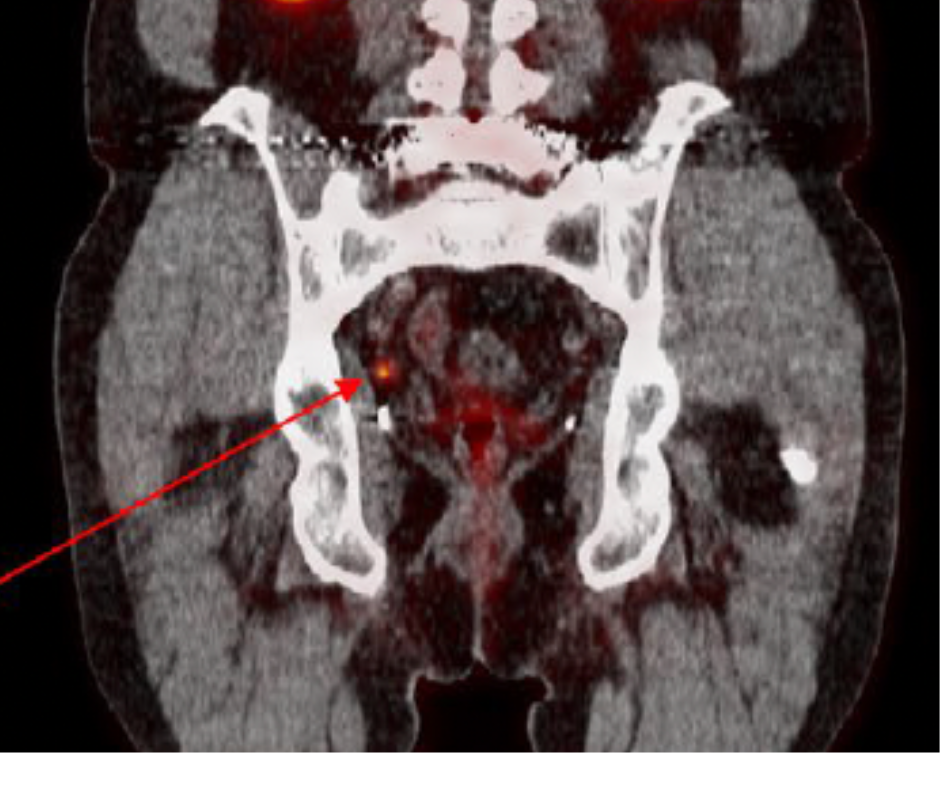

In a secondary analysis from the phase 3 CONDOR trial of men with biochemically recurrent prostate cancer, researchers found that utilizing piflufolastat F 18, a prostate-specific membrane antigen (PSMA)-targeted radiopharmaceutical, prior to positron emission tomography (PET) scanning led to changes in intended management in 39.1 percent of patients with a prostate-specific antigen (PSA) level below 0.5 ng/mL.1,2

For the study, presented recently at 2023 American Society of Clinical Oncology (ASCO) Genitourinary Cancers (GU) Symposium in San Francisco, researchers reviewed data from a subset of 69 patients from the CONDOR trial who had a PSA level below 0.5 ng/mL.1 Prior to PET imaging, the patients received a single dose injection of piflufolastat F 18 (PYLARIFY, Lantheus Holdings). Patients also completed pre- and post-imaging questionnaires about the intended management of their prostate cancer, according to the study.

The researchers noted that piflufolastat F 18 led to changes in intended treatment for 27 patients (39.1 percent). For 20 of the 27 patients (74.1 percent), the changes resulted in an escalation of treatment from either local salvage therapy to systemic therapy, or a shift from observation to initiating treatment. The study authors noted that piflufolastat F 18 identified lesions in 18 of the 20 patients who had an intensification of treatment.1